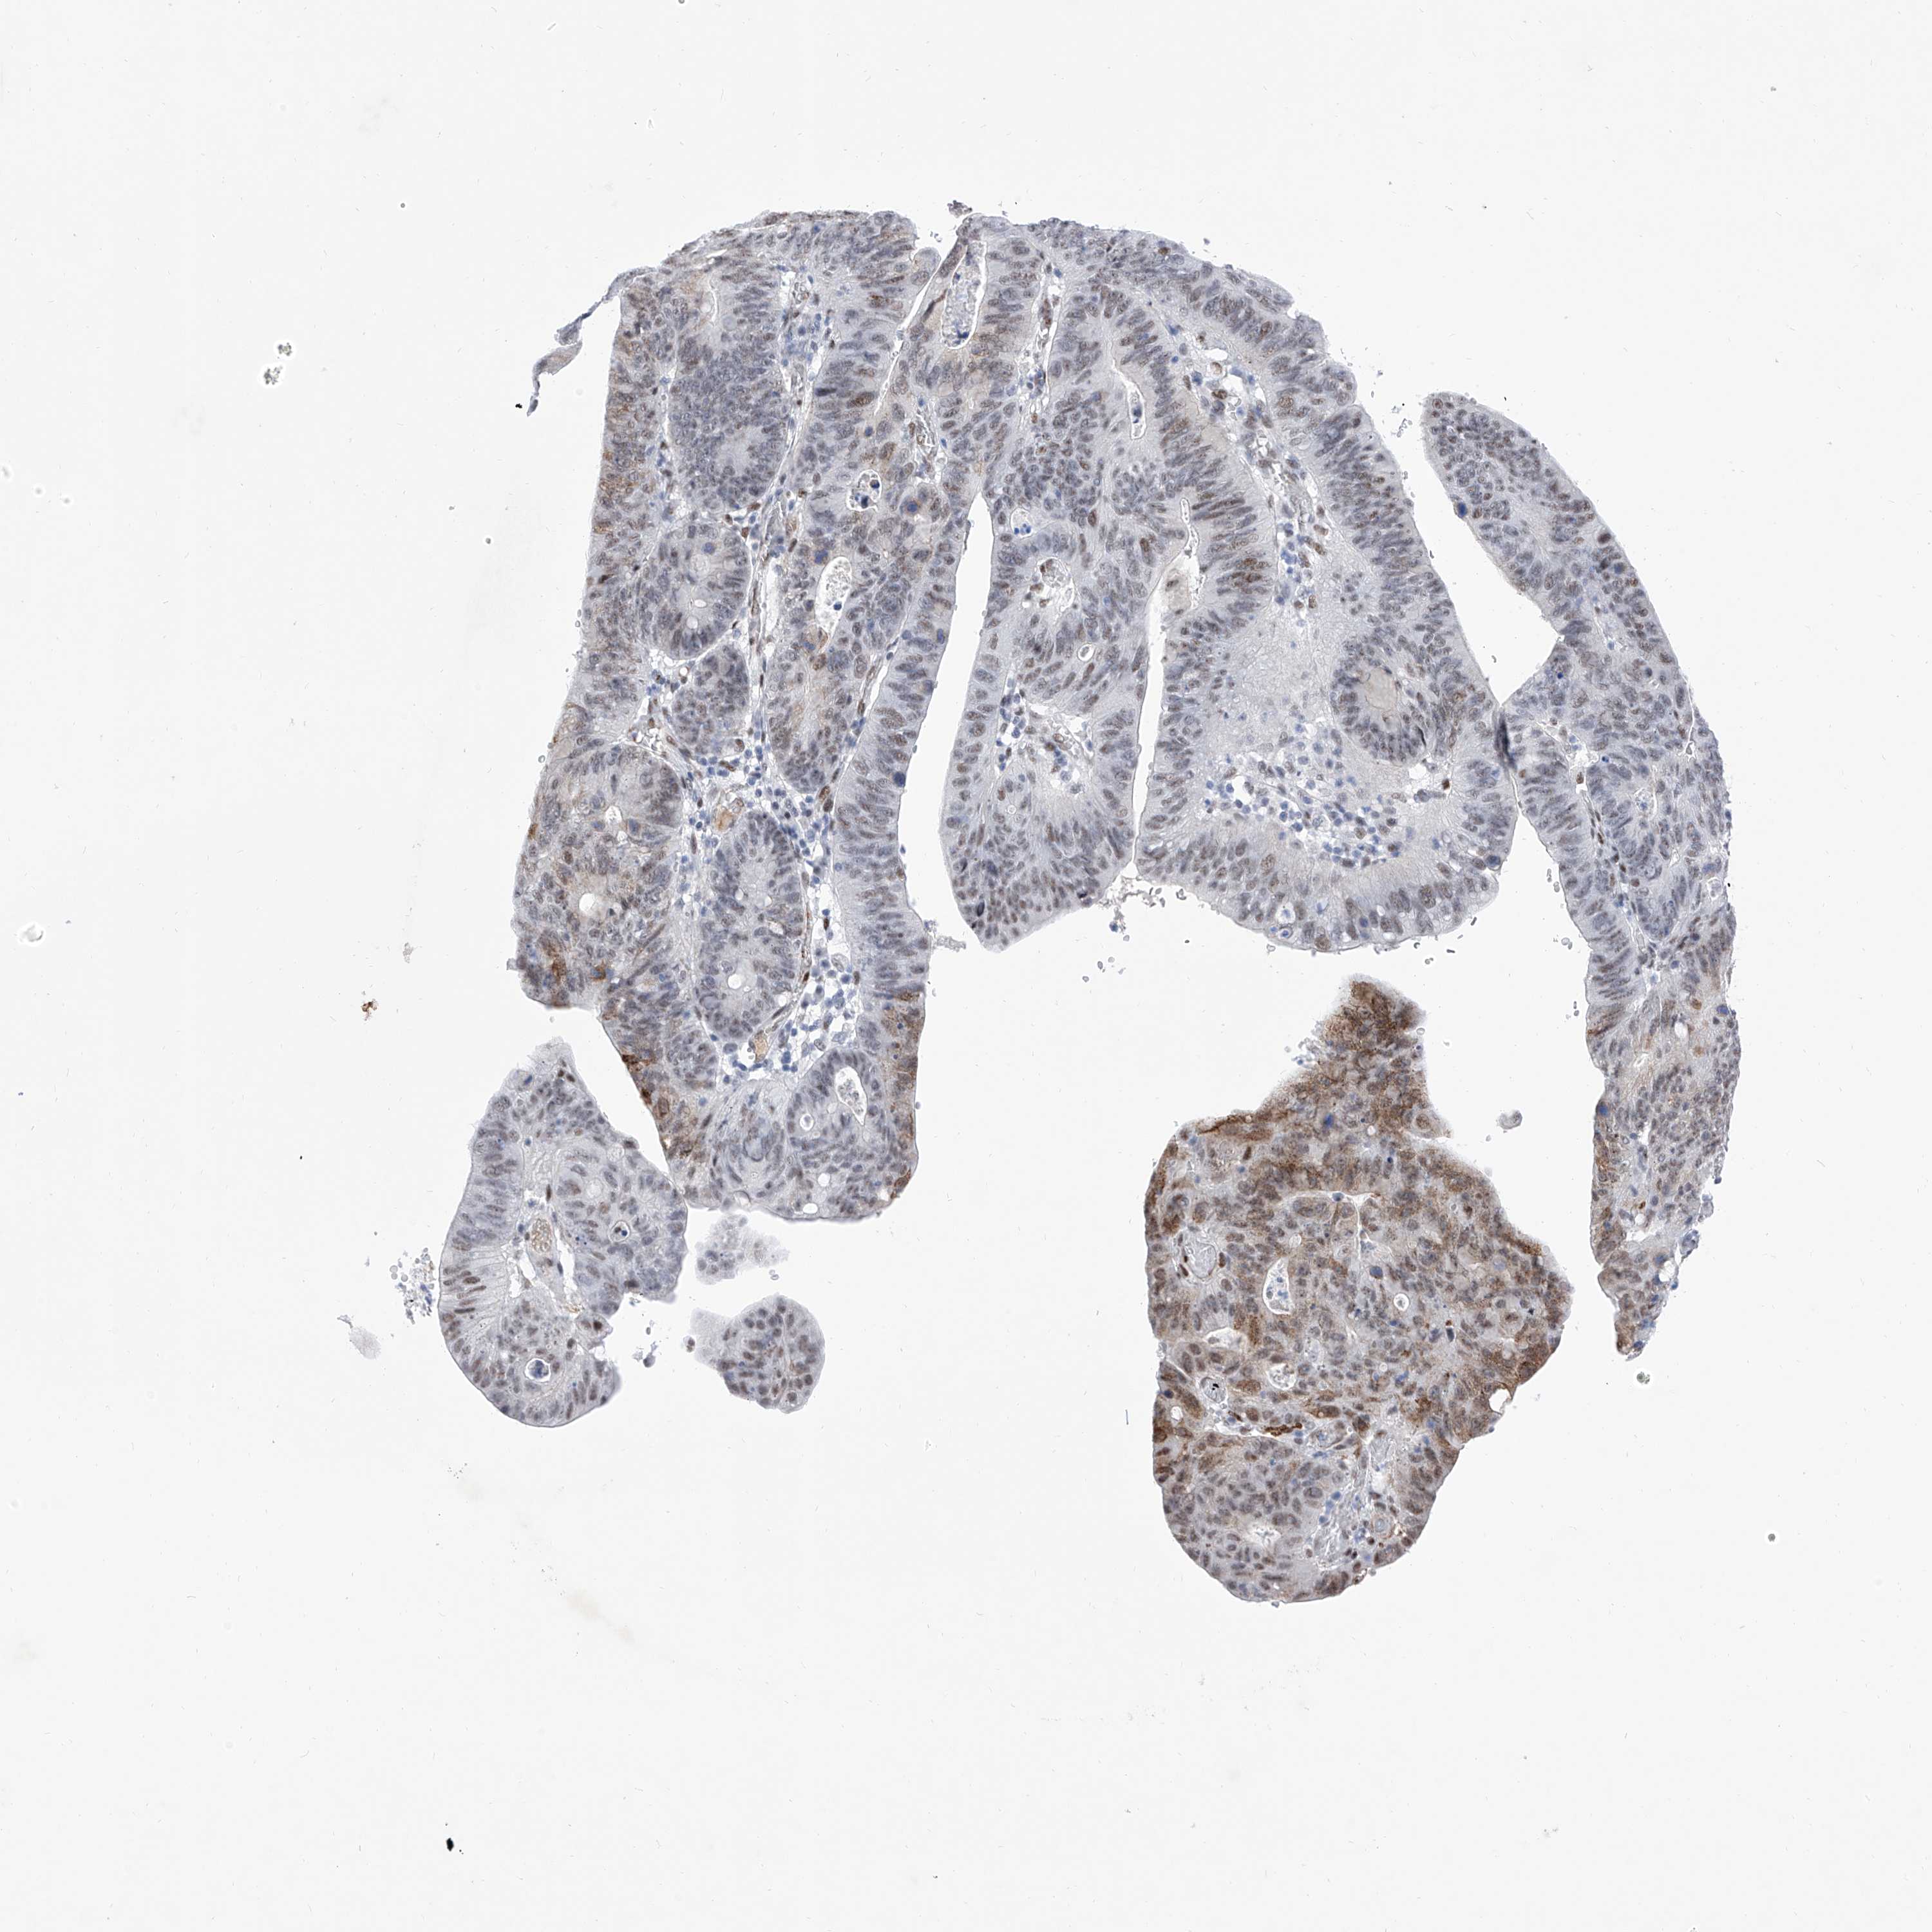

STOMACH CANCER - Protein expressioni

A mouse-over function shows sample information and annotation data. Click on an image to view it in a full screen mode. Samples can be filtered based on level of antibody staining by selecting one or several of the following categories: high, medium, low and not detected. The assay and annotation is described here.

Note that samples used for immunohistochemistry by the Human Protein Atlas do not correspond to samples in the TCGA dataset.

Antibody stainingi

Antibody staining in the annotated cell types in the current human tissue is reported as not detected, low, medium, or high, based on conventional immunohistochemistry profiling in selected tissues. This score is based on the combination of the staining intensity and fraction of stained cells.

Each image is clickable and will lead to virtual microscopy that enables deeper exploration of all samples and also displays staining intensity scores, fraction scores and subcellular localization as well as patient and tissue information for each sample.

Antibody HPA031619

Staining

High

Medium

Low

Not detected

Intensity

Strong

Moderate

Weak

Negative

Quantity

>75%

75%-25%

<25%

None

Location

Nuclear

Cytoplasmic/membranous

Cytoplasmic/membranous,nuclear

Adenocarcinoma, NOS